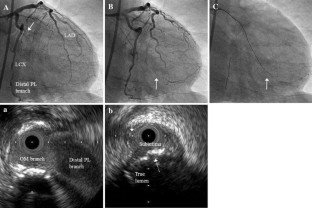

We describe an initial clinical chronic total occlusion (CTO) case in which CTO-specific intravascular ultrasound (IVUS): Navifocus WR was useful for navigating the second guidewire into the true lumen under the IVUS observation from the subintimal space.

Fig. 2